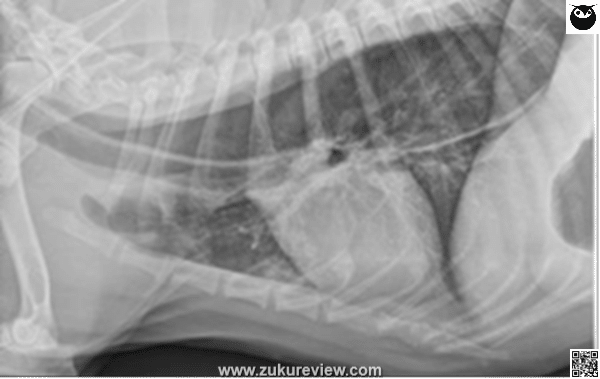

This is megaesophagus (ME) in a dog, which may be caused by myasthenia gravis (MG), esophagitis, hypoadrenocorticism, hypothyroidism, and a variety of autoimmune or congenital disorders. ME may be idiopathic. ME causes regurgitation of esophageal contents and aspiration pneumonia.

Radiograph image courtesy of Dr. Terri DeFrancesco, Copyright 2022, All rights reserved.